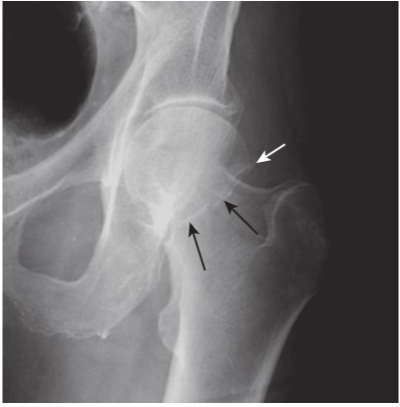

Fracture versus epiphyseal plate.

Fracture lines (blackarrow)tend to be straighter in their course and more acute in their angulation than any naturally occurring lines, such as the epiphyseal plates in the proximal humerus (white arrows). Because the top of the metaphysis has irregular hills and valleys, the epiphyseal plate has an undulating course that will allow you to see it in tangent, both on the anterior and posterior margins of the humeral head. This gives the mistaken appearance that there is more than one epiphyseal plate.